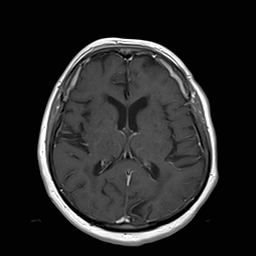

(a) Guide 𝑮𝑮\boldsymbol{G}

Refer to caption

(b) Input 𝑰𝑰\boldsymbol{I}

(c) Guidance map 𝑴𝑴\boldsymbol{M}

(d) Prediction 𝑷𝑷\boldsymbol{P}

(e) Ground truth

(f) Guide 𝑮𝑮\boldsymbol{G}

(g) Input 𝑰𝑰\boldsymbol{I}

(h) Guidance map 𝑴𝑴\boldsymbol{M}

(i) Prediction 𝑷𝑷\boldsymbol{P}

(j) Ground truth

Figure 2: Inputs and outputs of the guided filtering pipeline based on the WDSR network. T1 & T2 MRI pairs (a)-(e) and CT & MRI projection images (f)-(j).